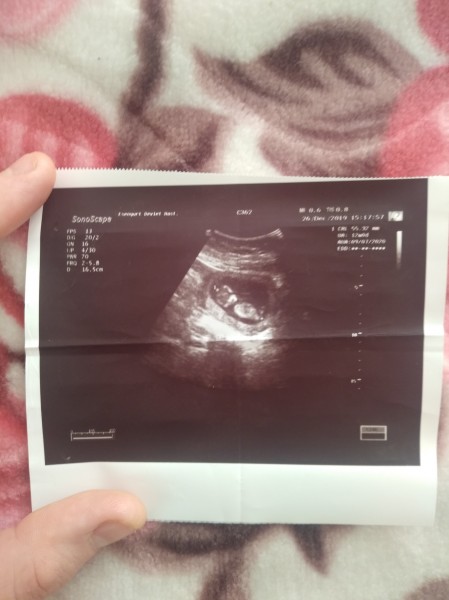

12 haftalık bebek kaç cm olur. Etiketler 12 hafta hamilelik 12 haftada bebek kaç cm olur 12 haftalık bebeğin boyu 12 haftalık bebeğin cinsiyeti 12 haftalık bebek 12 haftalık bebek görüntüsü 12 haftalık bebek kaç cm 12 haftalik bebek kac cm olur 12 haftalık bebek kaç gramdır 12 haftalik bebek kac mm olur 12 haftalık gebelik 12 haftalık gebelik cinsiyet 12. Boyunda ve 29 gram ağırlıktadır. Haftasında boyu 8 cm olmakta ağırlığı ise 18 gr olmaktadır. Bebeğiniz 2 ay 25 günlük.

12 haftalık bebek kaç aylık olur diye merak ediyorsanız baştan bilmenizde fayda var. 12 haftalık bebek boyu geçen haftalara göre hızlı bir şekilde bir hayli büyüdü. 12 haftalık bebek yaklaşık 6 5 cm. Baş bölümünden kalçaya kadar olan bölüm ölçüldüğü zaman bebeğin boyu yaklaşık olarak 6 cm dir.

Bacaklar anne karnında bükülü vaziyette bulunduğu için bacaklar ölçüye dahil edilmez. Genellikle bebeklerdeki kilo artışı boylara nazaran daha hızlıdır.